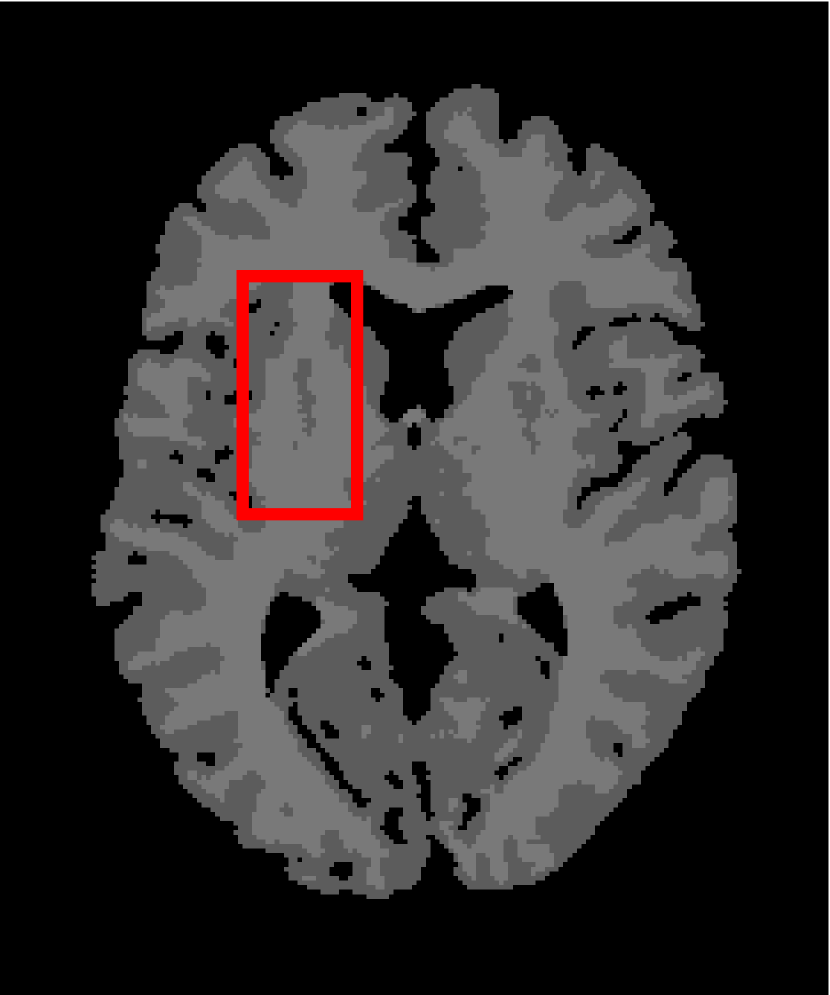

Next, we representatively segment five medical images from BrianWeb. They are represented as five slices in the axial plane with a sequence of 70, 80, 90, 100 and 110, which are generated by T1 modality with slice thickness of 1mm resolution, 9% noise and 20% intensity non-uniformity. Here, we set c=4𝑐4c=4 for all cases. The comparison between WRFCM and its peers are shown in Fig. 9 and Table II. The best values are in bold.

Figure 9: Segmentation results on five medical images. The parameter: ϕ=5.35italic-ϕ5.35\phi=5.35. From top to bottom: noisy images, ground truth, and results of FCM_S1, FCM_S2, FLICM, KWFLICM, FRFCM, WFCM, DSFCM_N, and WRFCM.

By a view of the marked red square in Fig. 9, we find that FCM_S1, FCM_S2, FLICM, KWFLICM and DSFCM_N are vulnerable to noise and intensity non-uniformity. They give rise to the change of topological shapes to some extent. Unlike them, FRFCM and WFCM achieve sufficient noise removal. However, they produce overly smooth contours. Compared with its seven peers, WRFCM can not only suppress noise adequately but also acquire accurate contours. Moreover, it yields the visual result closer to ground truth than its peers. As Table II shows, WRFCM obtains optimal SA, SDS and MCC results for all five medical images. As a conclusion, it outperforms its peers visually and quantitatively.